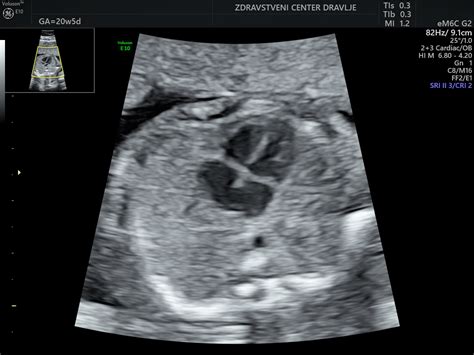

17. do 20. teden nosečnosti: Rast in oblikovanje telesaPlod je v obdobju hitre rasti, glava in telo sta v bolj proporcionalnih razmerjih, pod kožo se tvori maščevje, ki mu bo po rojstvu pomagalo zadrževati toploto. Zmožen je obrazne mimike. Sliši zunanje in notranje zvoke. Od glave do trtice meri 14 cm, skupno pa do 20 cm v dolžino, tehta do 190 g. Pri deklici so razvita rodila, pri dečku se pričenja razvoj prostate in spuščanje testisov iz medenice v mošnjo. Možgani se intenzivno razvijajo, intenzivna rast ploda se nadaljuje. Tudi nosečnice, ki so prvič noseče, bodo morda že lahko prvič občutile gibe ploda. V tem času se običajno opravi morfološki ultrazvočni pregled ploda ter določi lego posteljice. V 20. tednu plod meri približno 25 cm v dolžino in tehta približno 300 g. Na koži se pojavi verniks - bela mastna zaščitna snov. V tem tednu se razvija verniks (beli, mastni, sirasti premaz), ki ščiti plod. Vsa čutila se intenzivno razvijajo. Pri teh tednih se lahko pojavi bolečina krožne vezi, ki podpira maternico. Bolečina nastane zaradi rasti maternice in je popolnoma normalna. Lahko se pojavi ob sunkovitem gibu.